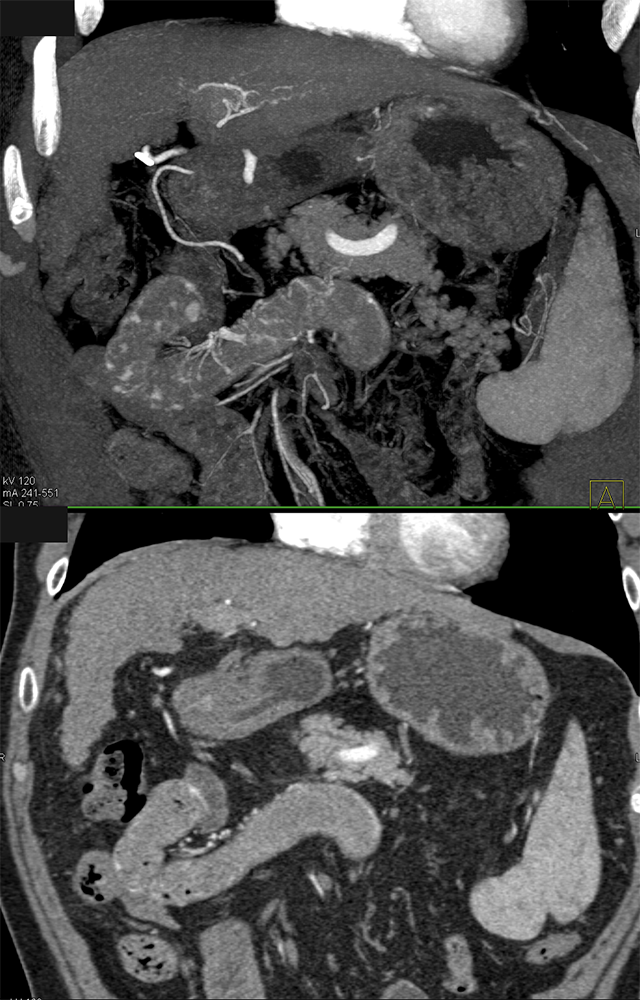

GI Bleed ![]() |

![]() |

GIST Tumor Duodenum ![]() |